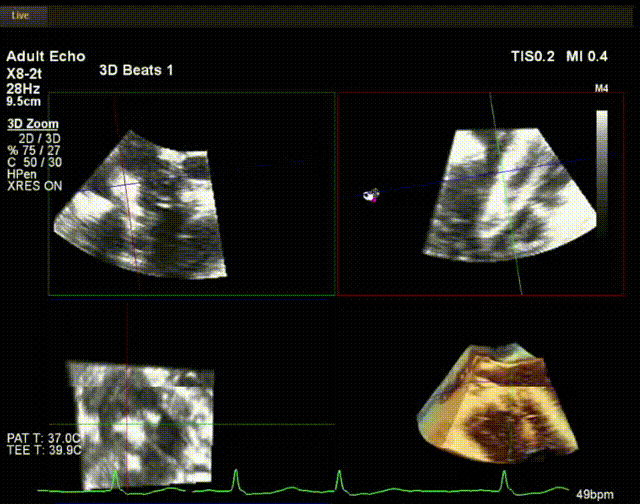

術中超聲